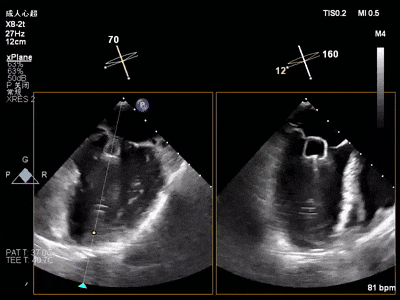

术中超声要点:

术前术后对比图:

术前

术后

术后,出院检查报告显示夹子位置固定,无移位,二尖瓣轻度反流,左室大小和LVEF值正常范围,左室壁运动分析未见明显异常。术后两个月随访检查,状态稳定,夹子位置固定,二尖瓣轻度反流,左室大小和LVEF值正常范围,左室壁运动分析未见明显异常(左室壁运动记分指数1分)。